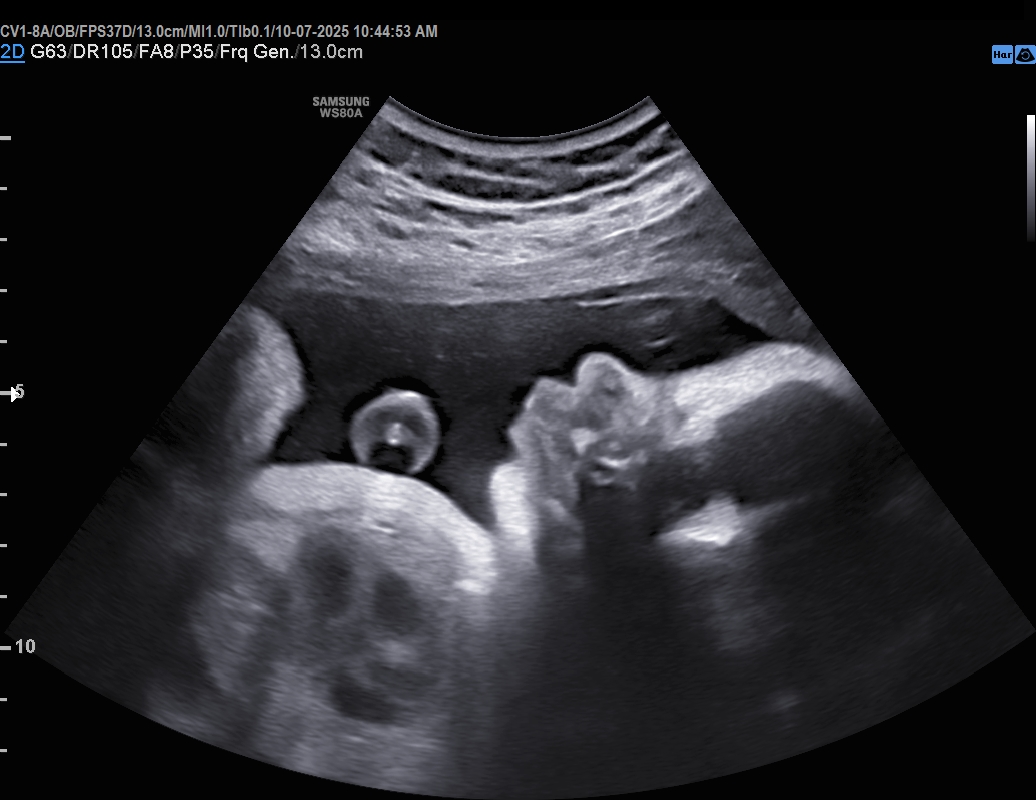

We are an elective ultrasound studio that specializes in early gender determination and High Definition ultrasounds.

• 2D ultrasounds $50-$75